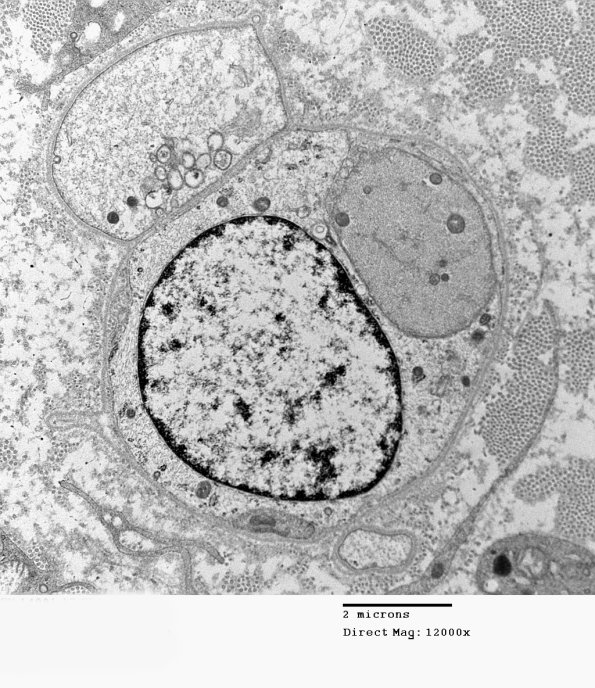

The completion of the demyelinating process results in naked axons which may be difficult to separate from adjacent Schwann cell processes at low magnifications. (electron micrographs)